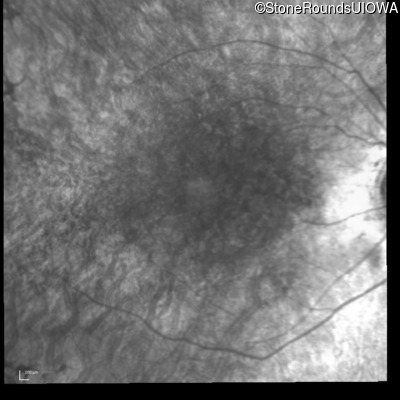

Infrared Fundus Photograph - Right - 20/60 +1 sc

Exemplar